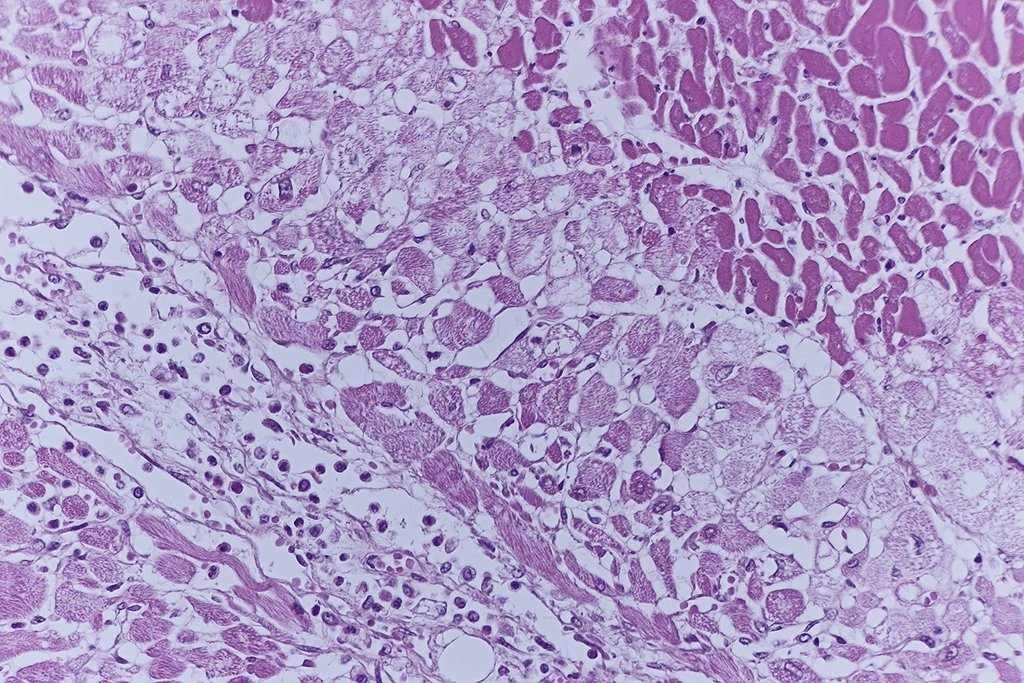

Bild 3 ist eine Übersicht eines Infarktes und man erkennt schon Unterschiede

in der HE Färbung. In der Vergrößerung wird man bei 1 einen deutlichen

Verlust der Herzmuskelfaserstruktur mit Hypereosinophilie und Verlust der

Querstreifung und der Zellkerne finden, und bei 2 eine Einwanderung von

Entzündungszellen (Bild 4 und 5, Paraffin, HE).

Die Bilder 6, 7 und 8 zeigen nun die gleichen Bereiche in einem

Technovit-Schnitt von 1,5µ.